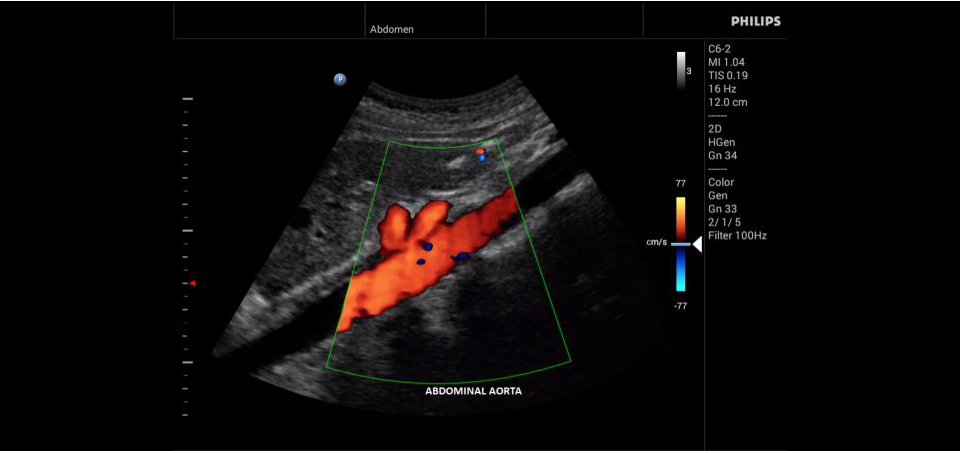

Philips InnoSight

Philips InnoSight увеличивает возможности сканирования во множестве мест оказания медицинских услуг. Благодаря данному УЗИ аппарату врачи могут не сомневаться в быстром выполнении обычных ультразвуковых сканирований во врачебном кабинете, клинике или больнице.

InnoSight позволяет перенести ультразвуковую диагностику непосредственно туда, где пациенту оказывается медицинская помощь, что повышает мобильность врачей. Этот компактный и легкий ультразвуковой аппарат позволяет чаще использовать возможности ультразвуковой диагностики и предоставляет широкий набор технологий для проведения углубленных исследований — программные пакеты для специализированного анализа, функции аннотирования и наборы готовых настроек для различных типов тканей.

Эргономичная система с высококачественными широкополосными датчиками Philips помогает повысить клиническую надежность результатов исследования и уровень оказания медицинских услуг. Аппарат можно перемещать вручную или с помощью тележки.

• Общие абдоминальные исследования;

• Исследования сосудов;

• Цветное допплеровское картирование

• Конвексный УЗИ датчик Philips C9-4v

• Конвексный УЗИ датчик Philips С6-2

• Конвексный УЗИ датчик Philips C5-2